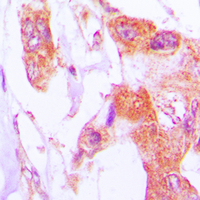

Immunohistochemical analysis of Involucrin staining in human lung cancer formalin fixed paraffin embedded tissue section. The section was pre-treated using heat mediated antigen retrieval with sodium citrate buffer (pH 6.0). The section was then incubated with the antibody at room temperature and detected using an HRP conjugated compact polymer system. DAB was used as the chromogen. The section was then counterstained with haematoxylin and mounted with DPX. -